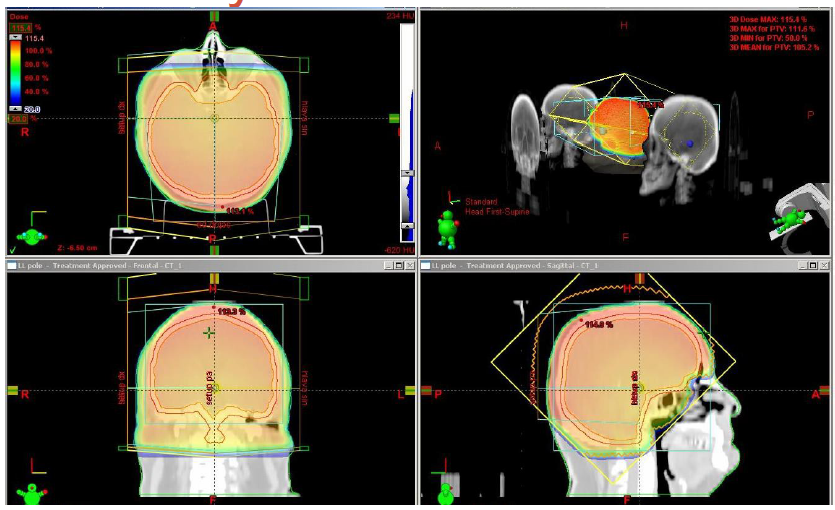

Metastázy CNS

- Stereotaktická radiochirurgie (SRS)

- U solitárních metastáz či oligometastáz

- Pokud není vhodná neurochirurgická resekce (ta vhodnější u mladších, v dobrém stavu, s periferně lokalizovanou lézí, při systémové kontrole nemoci)

- Leksellův gama-nůž (Homolka), CyberKnife (FN Ostrava), Linac s vybavením

Blanco AI, Cancers 2011

- Limitace počtem (obvykle do 3-4 ložisek) a velikostí (do 3 cm) ložisek

- Konzultace nemocnice Na Homolce: FAX - 257 272 972 (MR na e-PACS)

- Neinvazivní výkon, krátkodobá hospitalizace

- Naložení stereotaktického rámu, MR navigace, gama záření kobaltových zdrojů